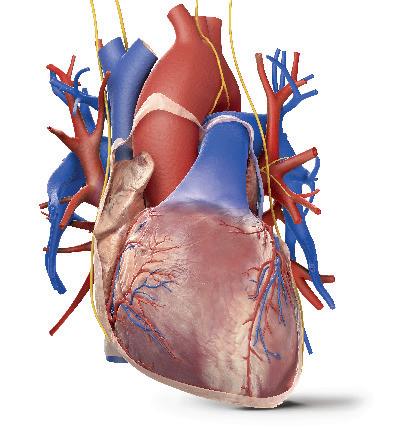

Lidé kdysi věřili, že srdce je sídlem myšlení a citu, dnes však víme, že je to svalová pumpa, která neúnavně pracuje, aby udržela krev v pohybu.

Na rozdíl od jiných svalů v těle, které si po námaze potřebují odpočinout a na chvíli se zastavit, je srdce předurčeno pracovat nonstop. Bije 70krát za minutu, 100 000krát za den, 40milionkrát za rok a za průměrný život napumpuje tolik krve, že by naplnila tři obří tankery. S každým úderem vytlačí okolo jednoho plného šálku krve a vyvíjí dostatečnou sílu, aby udrželo proudění krve ve 100 000 km cév v těle. Nepřetržitá dodávka čerstvé krve je pro tělní buňky životně důležitá, protože bez ní by během pár minut zahynuly na nedostatek kyslíku.

Bijící srdce

Srdce je uvnitř duté, má silné stěny z výkonných svalů a je asi tak velké jako zaťatá pěst – a stejně tak silné. Horní část srdce je připojena ke spleti vysoce odolných cév. Krev proudí dovnitř cévami zvanými žíly a naplňuje vnitřní prostory srdce. Když srdce bije, svalové stěny se stahují a vytlačují krev ven cévami zvanými tepny.

Aorta Tato velká céva vede okysličenou krev ze srdce.

Svalová stěna Srdce je poháněno silnou svalovou stěnou, která se při každém úderu stahuje.

Srdeční sval je obklopen pevným pláštěm zvaným osrdečník, který ho chrání před nárazy.

Uvnitř srdce

Srdce je rozděleno na dvě poloviny, takže pracuje jako dvě pumpy v jedné. Pravá polovina pumpuje odkysličenou krev do plic, aby zde nabrala vzdušný kyslík. Levá polovina pumpuje okysličenou krev do těla.

Srdeční cyklus

Každý úder srdce se skládá z několika pečlivě načasovaných kroků. Celá sekvence je řízena elektrickými impulsy, které se rychle šíří srdeční svalovou stěnou a spouštějí kontrakci svalových buněk.

1 Plnění

Mezi stahy vstupuje krev žilami do srdce a shromažďuje se v horních prostorách (síních).

Pravá síň se stahuje. Levá síň se stahuje.

Krev je tlačena do komor.

Věnčité tepny

Srdce pumpuje krev nejen do těla, ale do své vlastní svalové stěny. Srdeční sval velmi těžce pracuje a potřebuje vydatný přísun okysličené krve.

Poté, co dodá do svalové srdeční stěny kyslík a palivo, odtéká použitá krev žilami (znázorněnými modře).

Krev vracející se z těla. Krev vracející se z plic.

2 Síně se stahují Horní prostory se stahují a tlačí krev chlopněmi do dvou spodních prostor (komor).

proudí do těla. Krev proudí do plic.

3 Komory se stahují Nakonec se s velkou silou stahují komory a vytlačují krev do všech částí těla.